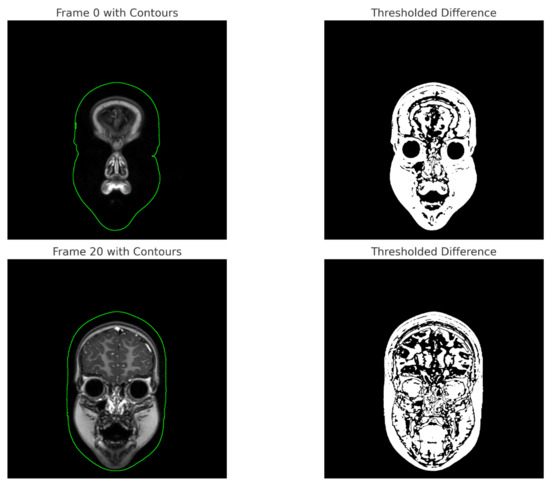

- Frame Extraction

- In the frontal plane, only the first frame is extracted without details about its content. In the sagittal plane, 10 frames are extracted at equal intervals, with a description of each frame’s content;

- Frame Content Description

- The frontal plane lacks a detailed description of the first frame, while the sagittal plane provides detailed descriptions of each of the 10 extracted frames, including scene context, perspective, motion, and interactions.

| Frame Extraction | Extracted first frame, no detailed content provided. | Extraction of 10 frames at equal intervals, with detailed description of each frame. |

| Frame Content Description | No detailed description of the first frame. | Detailed description of each of the 10 extracted frames, focusing on scene context, perspective, movement, and interactions. |